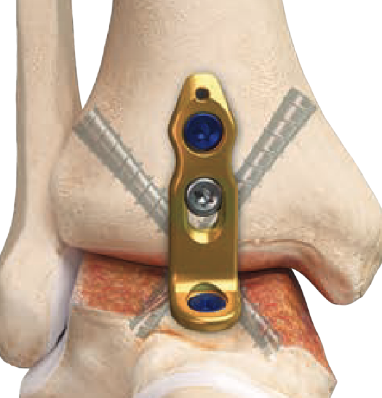

Anterior approach

Technique

Acumed anterior ankle fusion video

Arthrex surgical technique PDF

Anterior midline approach

- between tibialis anterior and EHL

- tibia and talar pins and ankle distractor

- debride joint surfaces

- fix with anatomically contoured anterior plate + screws